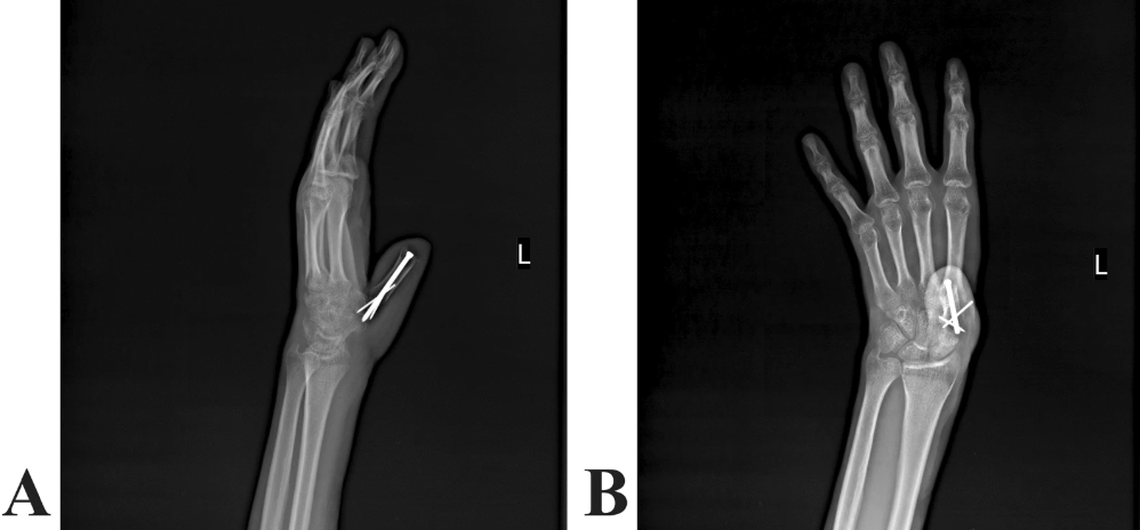

The thumb was reconstructed using the preserved bone and tissue from the man’s thigh, doctors said.

The thumb was reconstructed using the preserved bone and tissue from the man’s thigh, doctors said. Kafiabadi, et al (2025) Journal of Medical Case Reports

“After extensive physical therapy sessions, complex functions were restored to a reasonable level,” doctors said. “He can now pick up objects, such as a pen, with his reconstructed thumb and write on paper. The patient used his reconstructed thumb daily and expressed satisfaction with the results of the operations.”